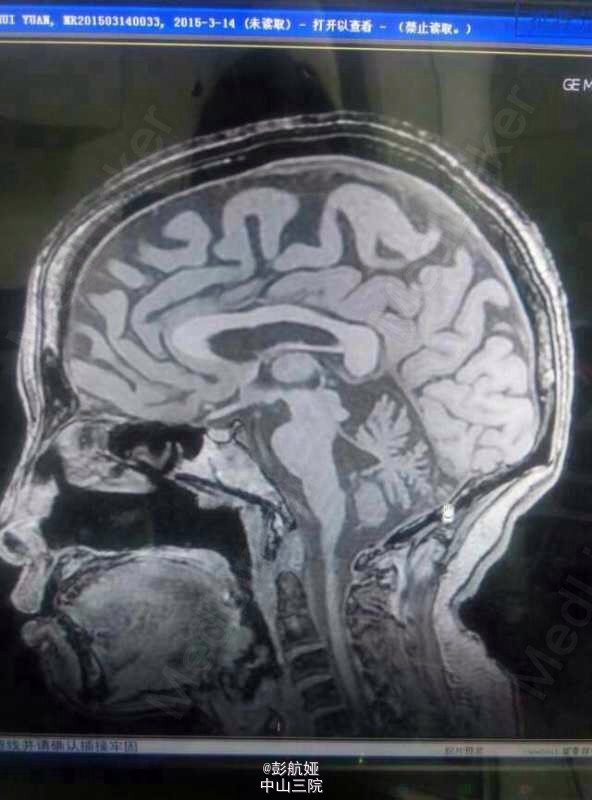

多系统萎缩-小脑型(MSA-C)

多系统萎缩

多系统萎缩MSA-C型1例

多系统萎缩C型一例

多系统萎缩?